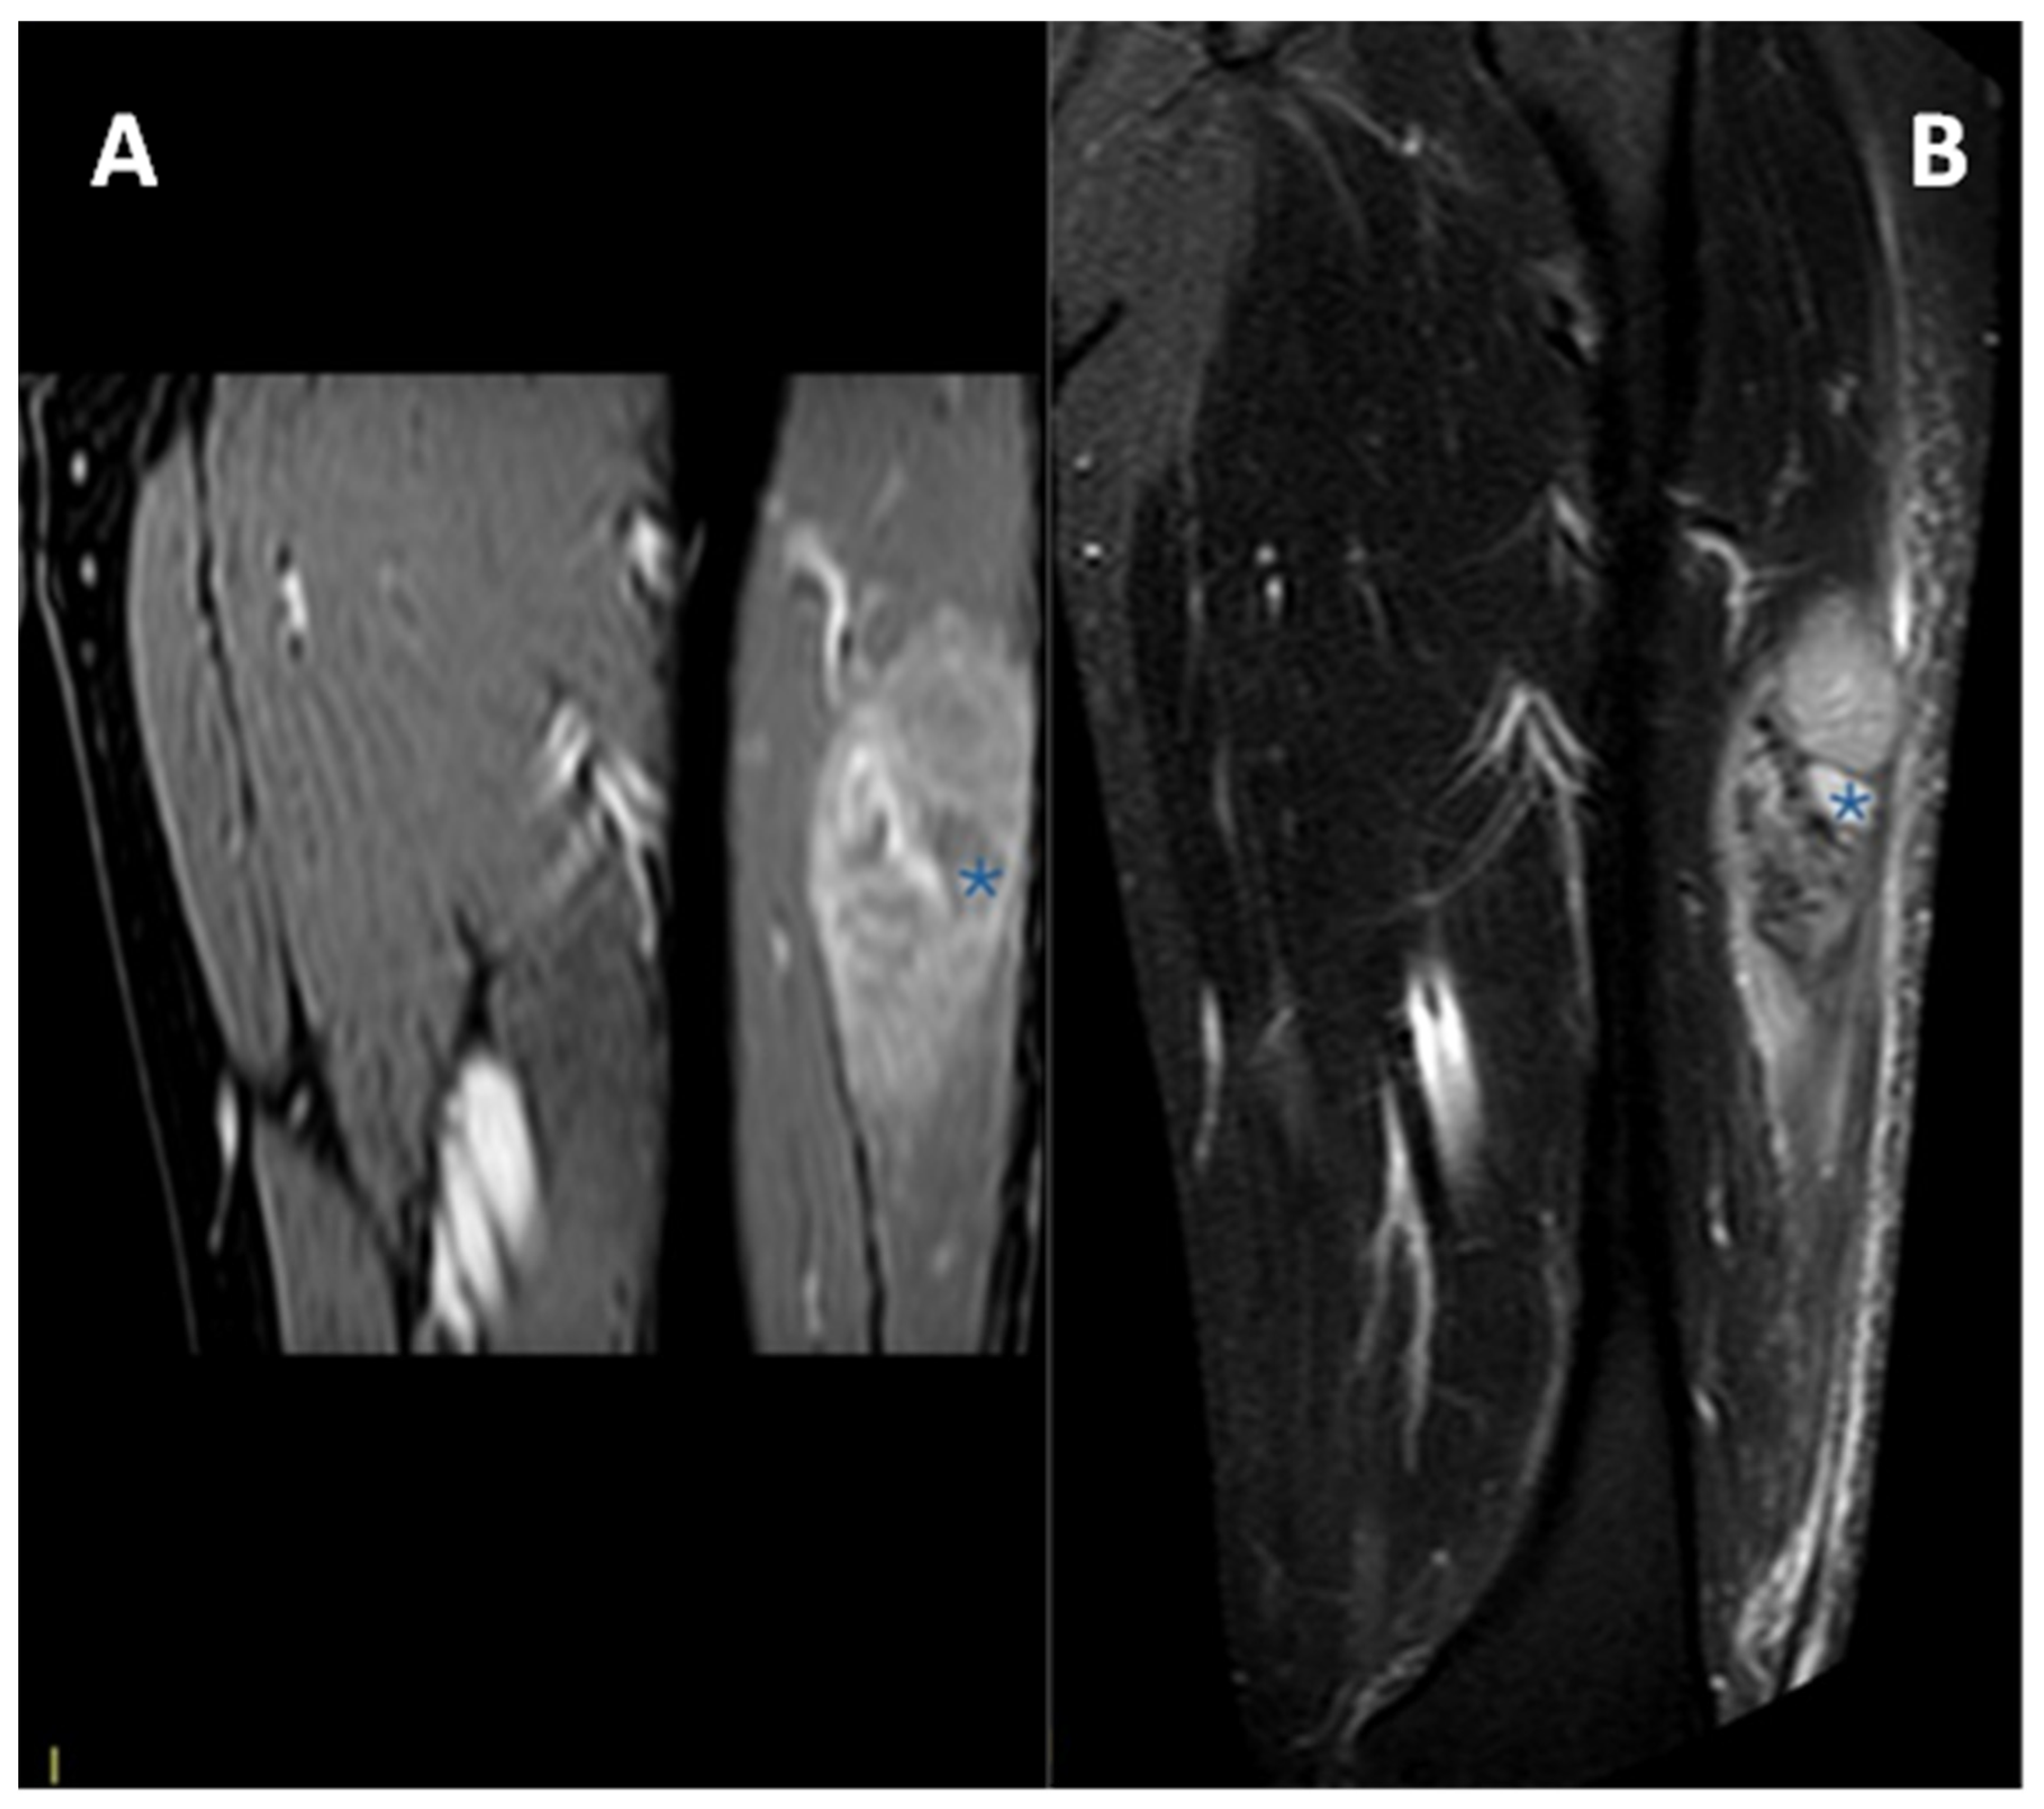

3.4. MRI Features

3.4.1. General MRI Features

3.4.2. Peritumoral Edema

3.4.3. Other MRI Features